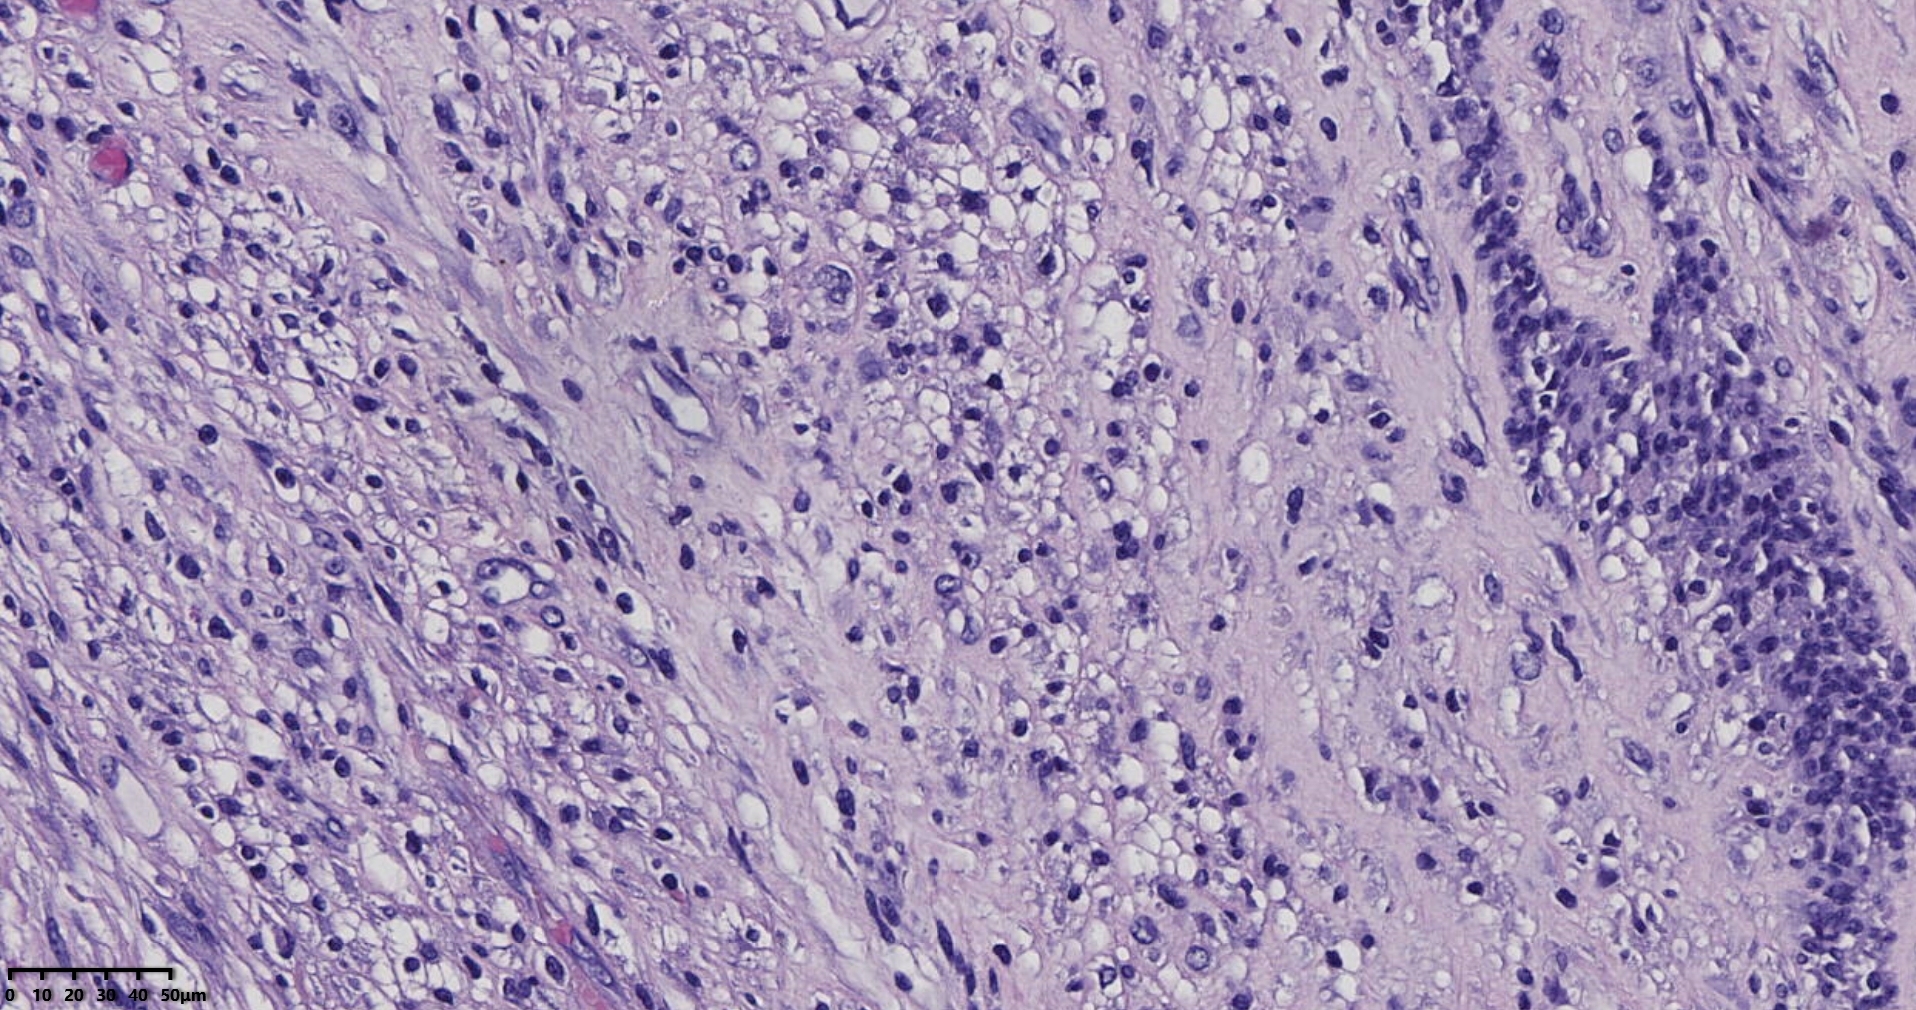

镜下所见小肿物无特殊,大肿物瘤细胞密集,中心区有变性、坏死,瘤细胞核有异型性。大肿物补充取材,发现,部分区域切面灰黄,这个区域,瘤细胞更密集,异型性更显著。肿物边缘有薄层正常平滑肌组织被覆,靠近边缘瘤细胞最密集,局部瘤组织内小血管较丰富。

会诊:考虑平滑肌肉瘤。

北医三院会诊:子宫平滑肌瘤伴红色变性可能性大,建议加做免疫组化及NGS检测进一步明确诊断。